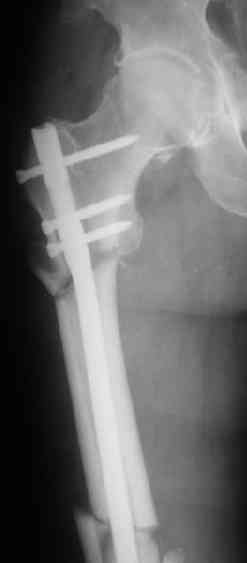

СМ> Если имеются под рукой Р-снимки, продемонстрируйте, плиз.

Вот несколько. С тисками и трубой на днях сделаем.

Гвозди с латерализованным проксимальным концом сейчас становится мэйнстримом, поскольку трохантерная точка входа во всех отношениях

благоприятнее f. piriformis.